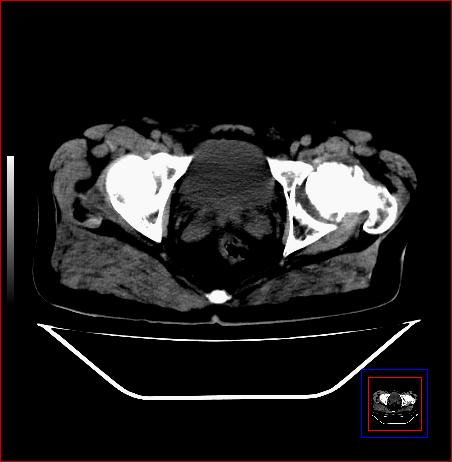

标题: CT15143:髋关节结核?

男,49,髋关节疼痛1年,无肺结核。

支持左侧髋关节结核合并轻度半脱位

骨质破坏,硬化,周围软组织脓肿,支持骨结核

骨质破坏,硬化,周围软组织脓肿,关节间隙增宽,支持骨结核

骨质破坏,硬化,周围软组织脓肿,关节间隙增宽,支持骨结核 .应与无菌坏死鉴别

可以是结核,也可以是无菌坏死,还可以是先天髋关节脱位,不结合临床病史,只凭图像鉴别,请各位老师指教。